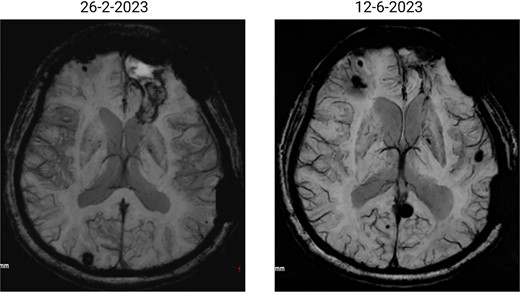

The patient has undergone multiple rounds of MRI and CT (Fig. 3) imaging examinations, the results of which have consistently shown a morphology suggestive of recurrent ICH. T2-weighted (Fig. 4) and susceptibility-weighted (SW) MRI (Fig. 5) showed many cerebral cavernous malformations (CCMs) scattered across both cerebral hemispheres, mainly located in the left parietal, frontal, and occipital lobes, with some lesions extending into the brainstem. Multiple lesions presented with a mixed signal intensity corresponding to different stages of haemorrhage and blood degradation products. There was noticeable hemosiderin deposition, indicating the presence of chronic microhaemorrhages. These deposits were particularly extensive in the left parietal lobe, corresponding to the site of the largest and most symptomatic haemorrhage. Regions of gliosis were observed near the haemorrhagic lesions, indicating long-term damage from previous haemorrhages. SWI confirmed the presence of multiple microhaemorrhagic lesions in the parenchyma and subcortical white matter, complicating the clinical picture.

SWI images of the brain. Brain angiography showing obvious vascular malformations. SWI images of the brain showing multiple haemorrhagic lesions with some active bleeding.